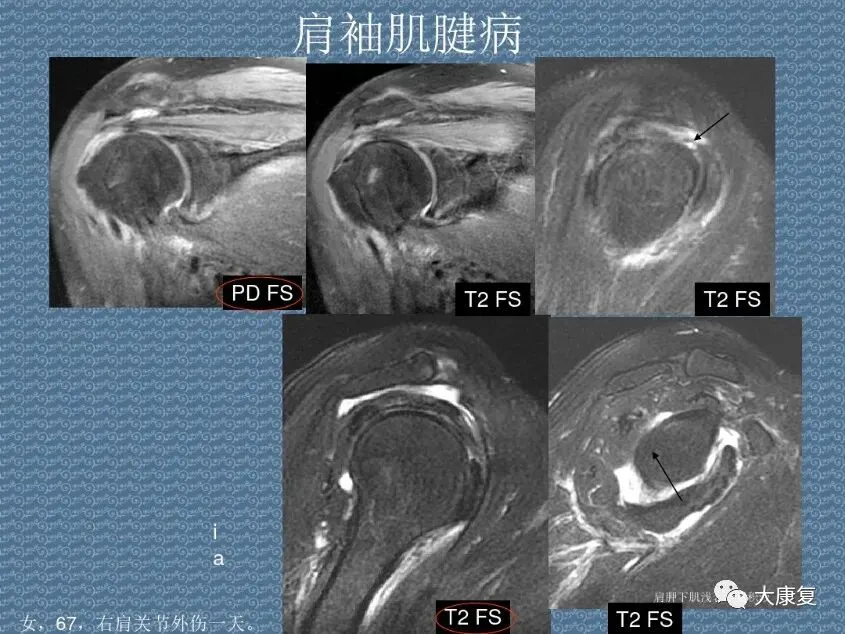

>PPT课件 | 肩关节的解剖结构和特点

PPT课件 | 肩关节的解剖结构和特点